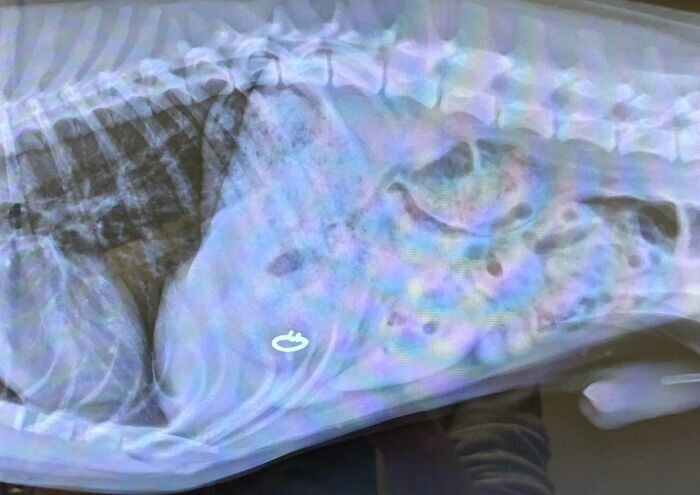

25. "Жена потеряла обручальное кольцо"